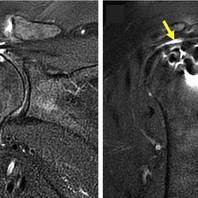

Un’alternativa è rappresentata da un palloncino riassorbibile introdotto come barriera fisica sopra il tendine riparato. Questo palloncino, chiamato Balloon Orthospace, funge da distanziatore tra l’acromion ed il tendine riparato consentendo di riportare la testa omerale in una posizione più anatomica. Ciò consente una migliore funzione del deltoide ed un movimento della spalla più fluido, permettendo una riabilitazione più agevole e meno dolorosa per il paziente, oltre che un minor rischio di rirotture dei tendini riparati.

Il palloncino Balloon Orthospace viene inserito nella spalla in artroscopia, al termine dell’intervento di riparazione dei tendini, senza aumentare invasività o rischi dell’intervento artroscopico.

Il palloncino viene con il tempo riassorbito dal corpo, tuttavia è stato dimostrato che anche dopo il suo riassorbimento il tessuto rimanente può comunque mantenere la riduzione della testa omerale e una migliore funzionalità della spalla. Studi recenti hanno dimostrato che anche 5 anni dopo l’intervento i pazienti mantengono ancora una buona mobilità e funzionalità della spalla operata.